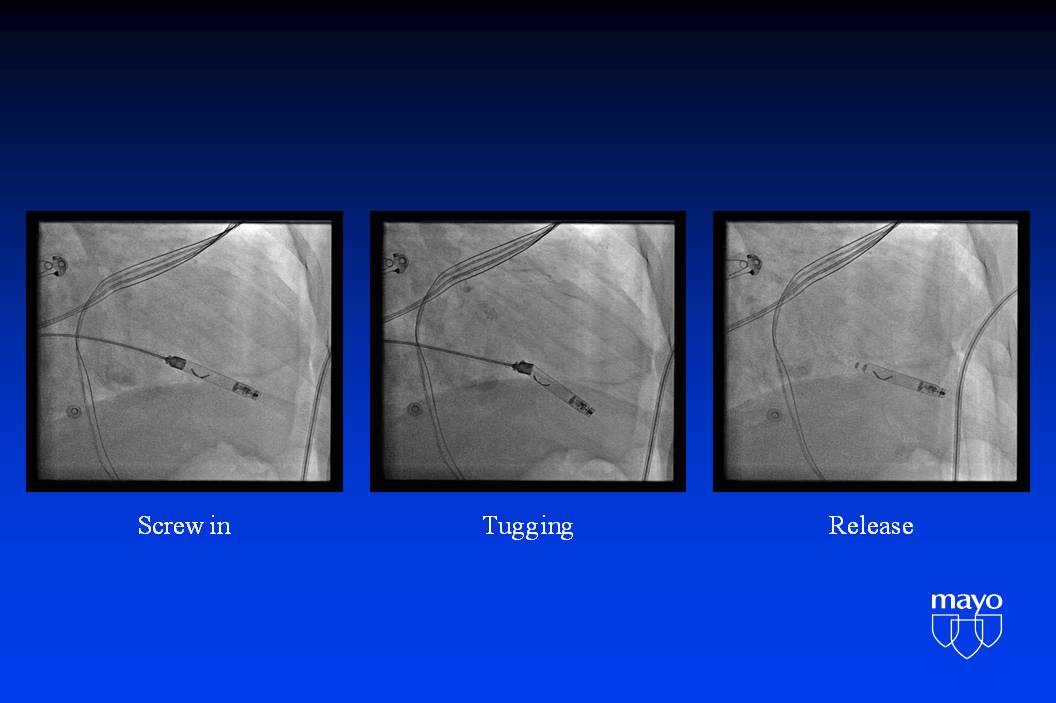

心脏起搏治疗:HRS 2015 新观点